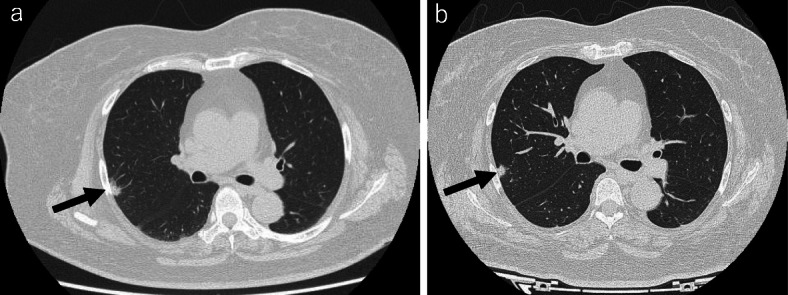

Chest computed tomography

A nodule shadow was recognized in the right superior lobe of the lung, but it was impossible to determine whether it was an inflammatory or neoplastic lesion (Fig. 1a). No meaningful lymph node swelling was seen in the mediastinum.

Fig. 1.

Chest computed tomography scan. a An image obtained 1 month before the LSG is shown. A 10-mm mass was observed in the superior lobe of the right lung (arrow). b An image obtained 2.5 months after the LSG is shown. No marked change in the size of the lung mass (arrow) was noted, but a reduction in the amount of subcutaneous fat was seen

LSG [6]: the procedure, which was performed under general anesthesia, involved longitudinal resection of the greater omentum, starting from the antrum at a point 4 cm from the pylorus along the greater curvature of the stomach and finishing at the His angle (Fig. 2a). After resecting the omentum, the stomach was resected on the side of the greater curvature using a surgical stapling device under endoscopic guidance (Fig. 2b). Thus, after surgically removing a section of the stomach, a small-diameter gastric tube, i.e., a small stomach, was produced. After reinforcing the staple line, endoscopy confirmed that there was no bleeding or contraction within the stomach. The operative time was 3 h and 24 min, and the amount of intraoperative blood loss was 10 mL. No complications were observed after the LSG, and sufficient nutritional guidance was provided. The patient was discharged from hospital 10 days after the surgery. The patient’s type-2 diabetes, dyslipidemia, and hypertension improved without medication after the LSG. Two and a half months after the LSG, her BW and BMI had reduced to 67.2 kg and 30.3 kg/m2, respectively, and her HbA1c level had normalized to 5.5% without medication (Table 1). Chest computed tomography showed no marked change in the size of the lung tumor and a reduction in the amount of subcutaneous fat (Fig. 1b). As safe surgery was judged to be possible, a decision was made to resect the lung tumor. Thoracoscopic right lung superior lobe resection was selected, as a quick pathological inspection performed during the operation revealed that the tumor was malignant (Fig. 3a, b). The operative time was 3 h and 42 min, and the amount of intraoperative blood loss was 5 mL. The patient was discharged from hospital 12 days after surgery with no complications. The tumor measured 12 × 10 × 6 mm. Papillary adenocarcinoma was detected during a pathological examination of the resected specimens. No metastases were found in the regional lymph nodes. The TNM stage was pl0, ly0, v0, br (-), PN0, sT1bN0M0 stage IA2.